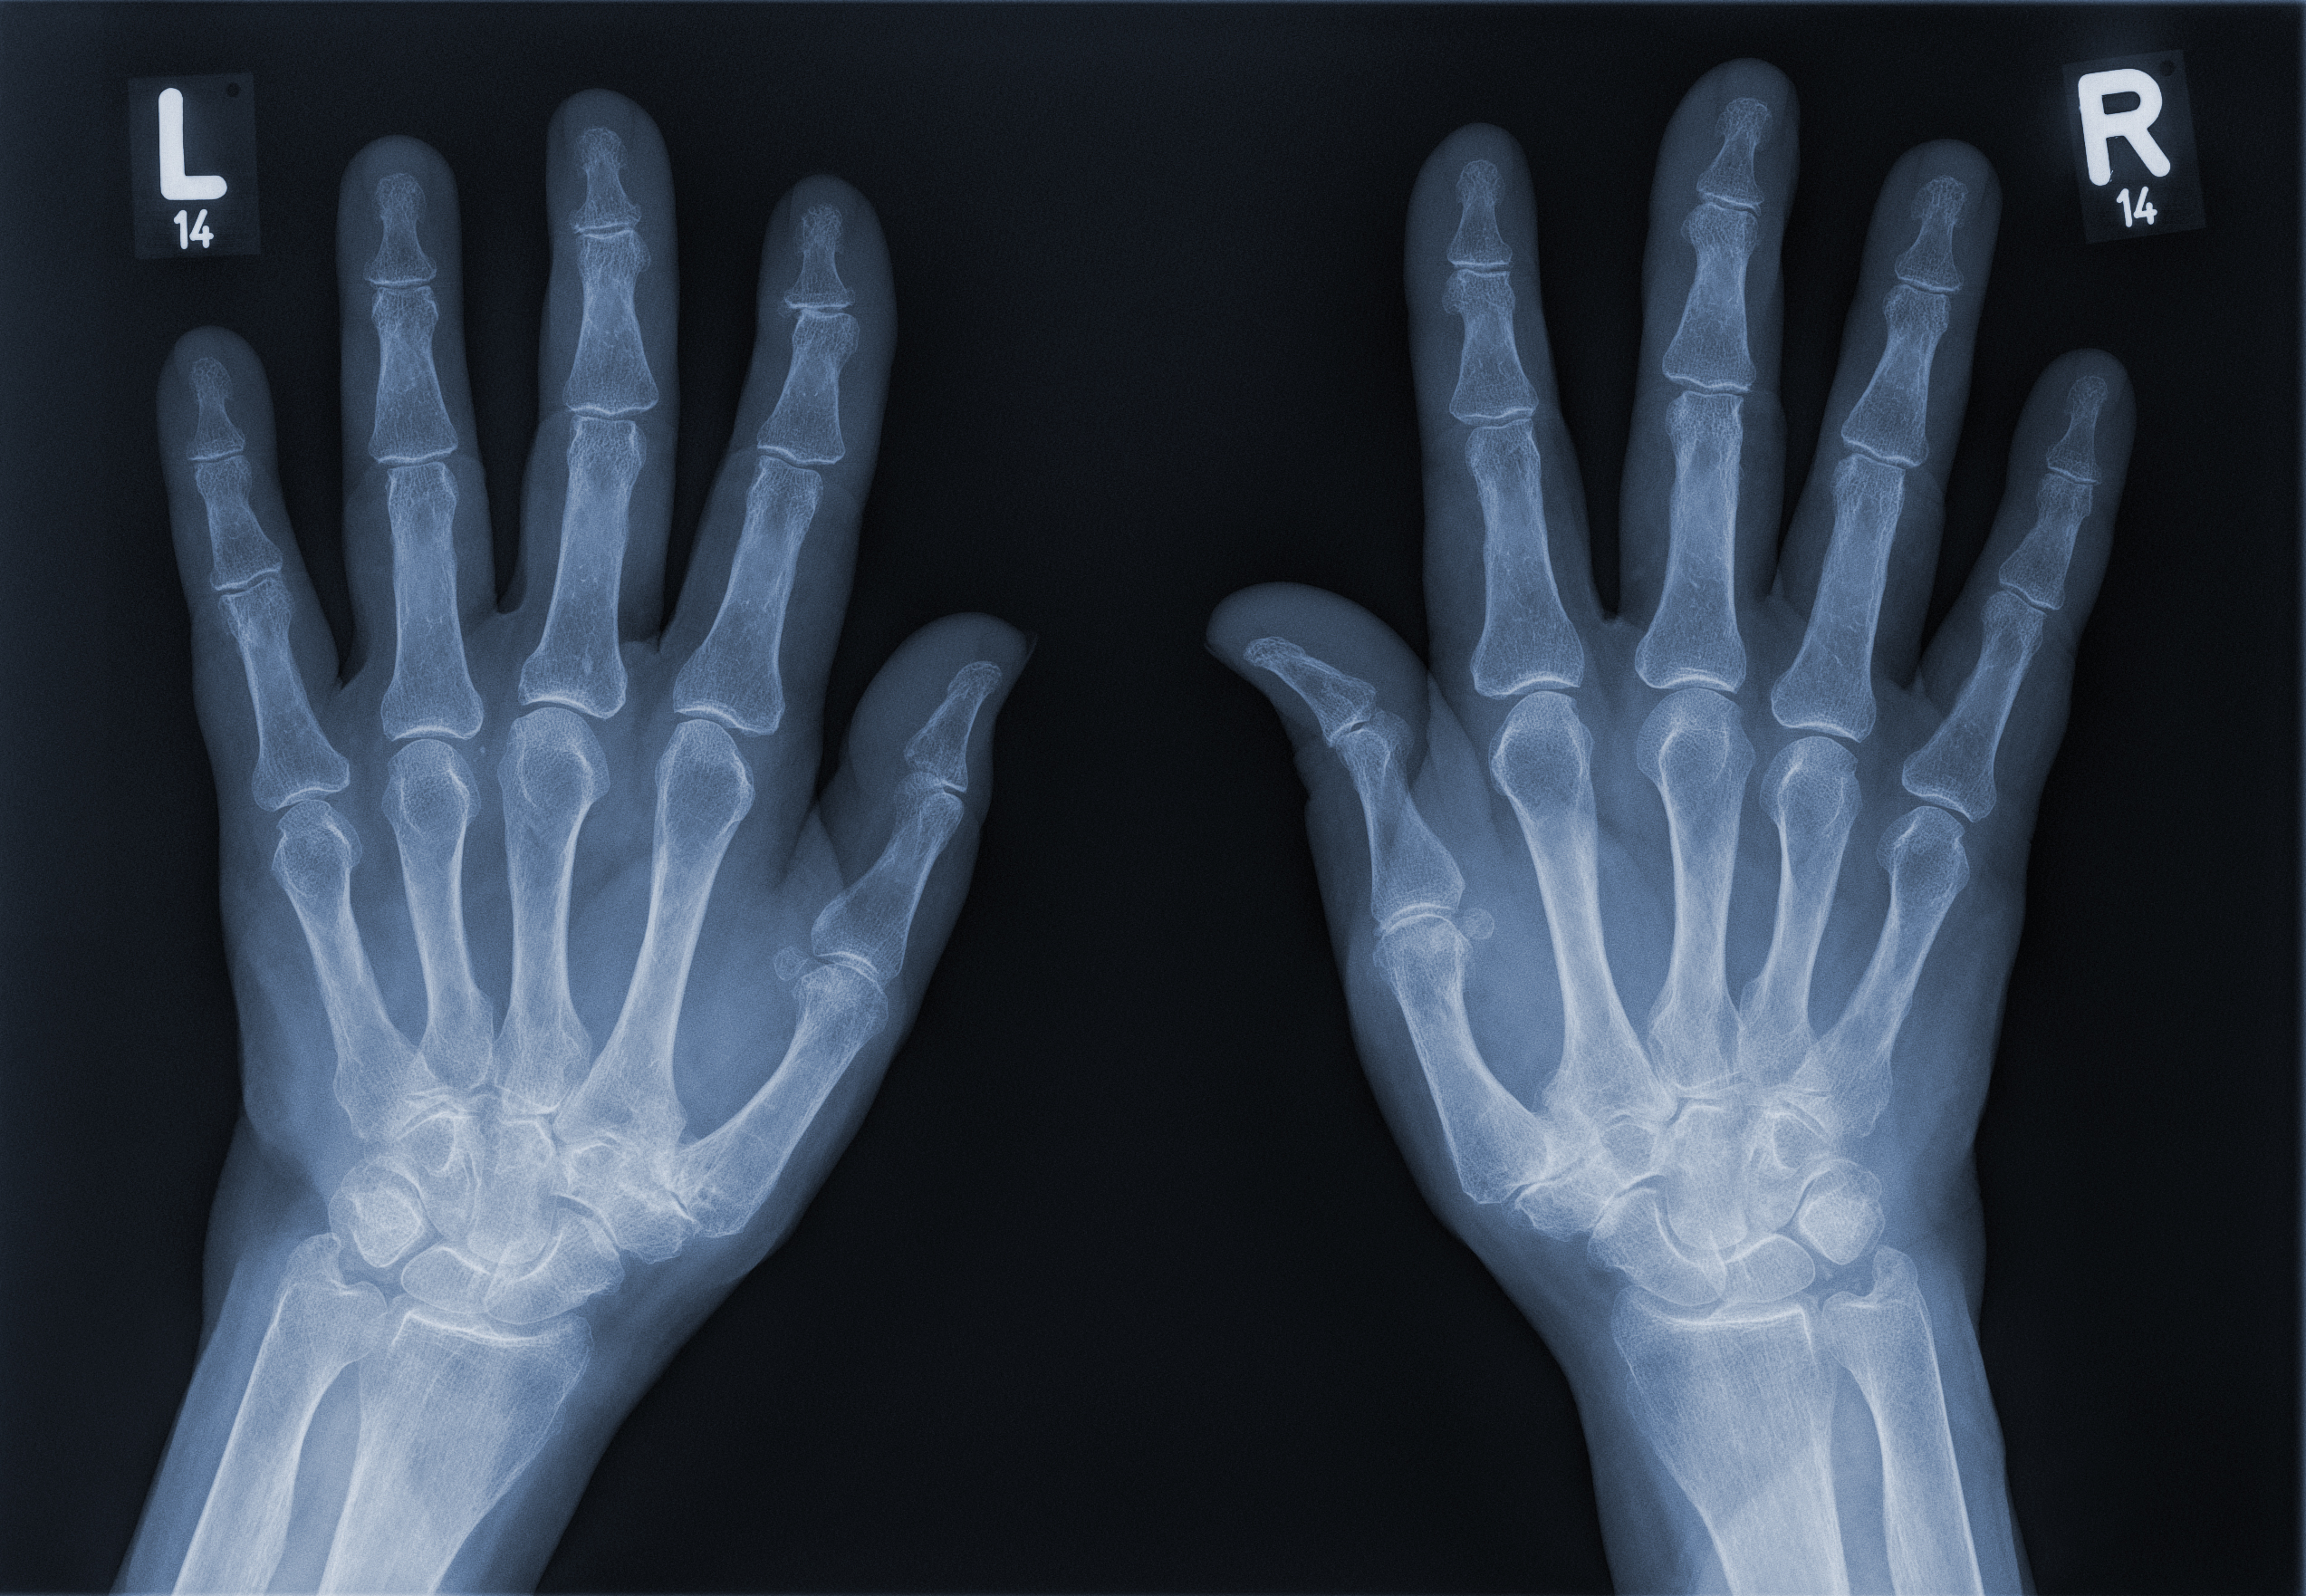

Es erfolgt eine klinische Untersuchung, sowie ein Röntgen, um die Diagnose zu sichern und den Eingriff zu planen. In Einzelfällen ist möglicherweise ein CT oder MRT notwendig, um den Zustand des Gelenks und der umgebenden Strukturen zu beurteilen.